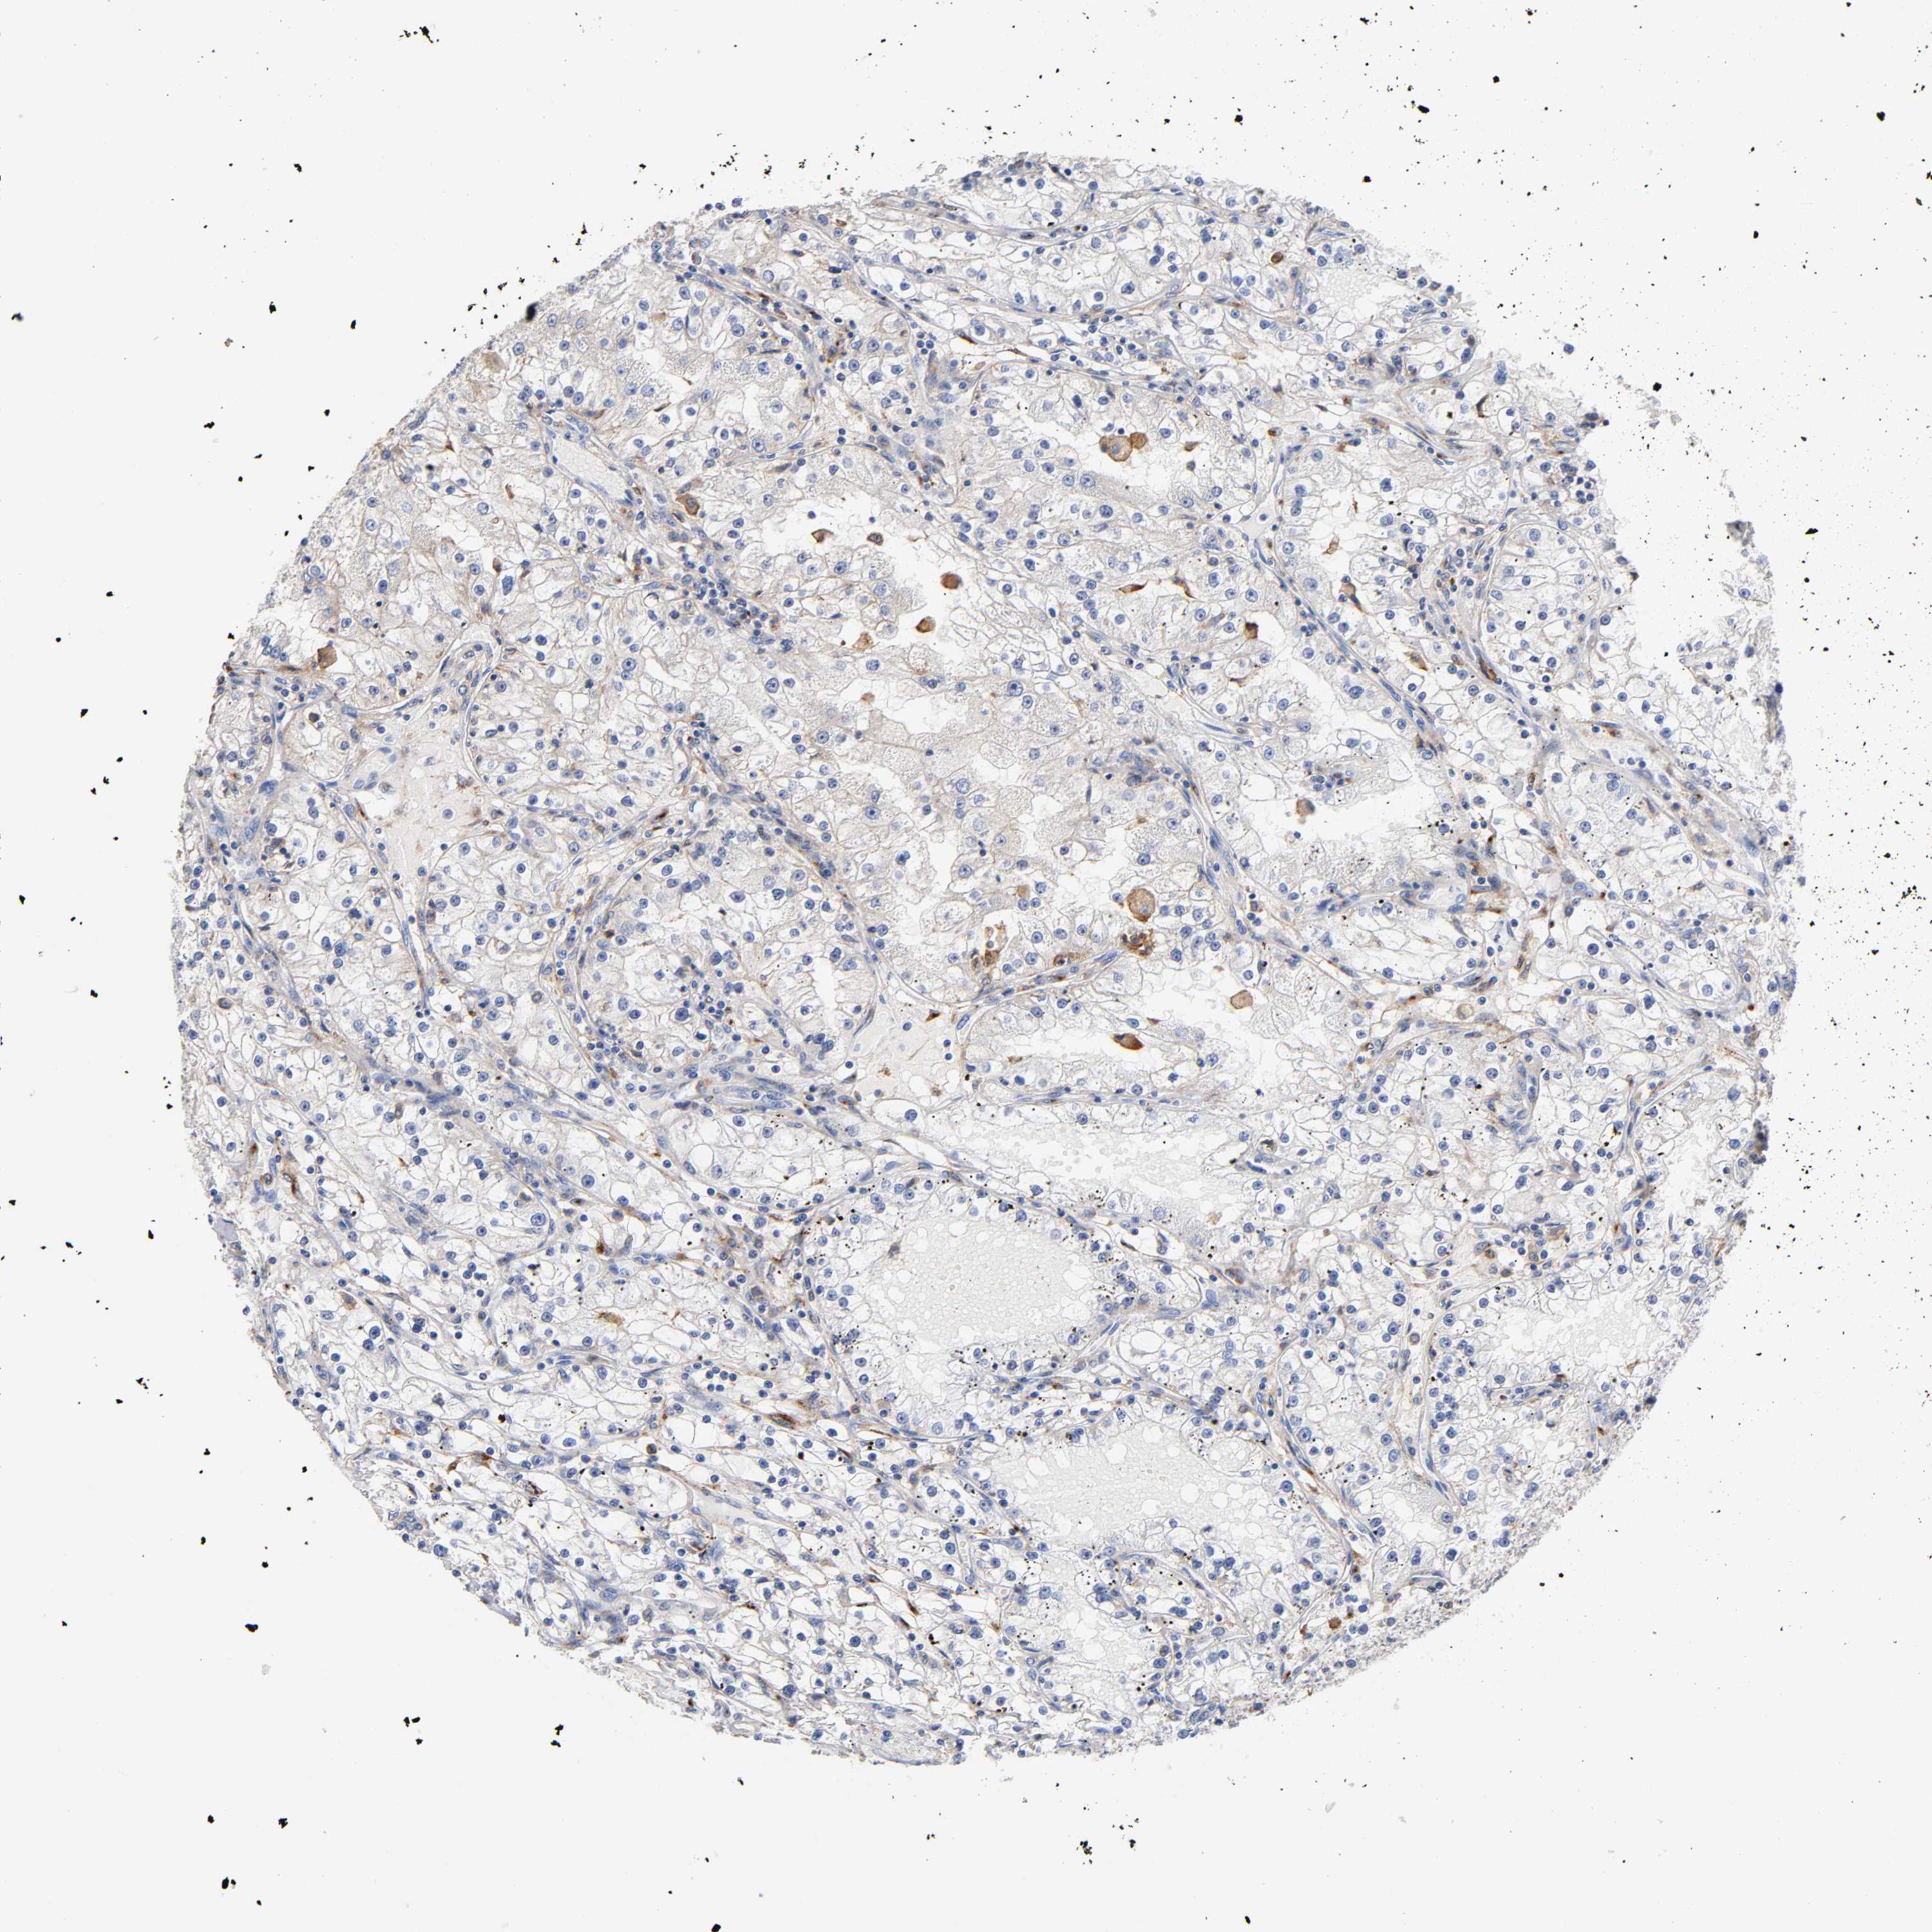

Renal cancer

Kidney renal clear cell carcinoma

KIDNEY RENAL CLEAR CELL CARCINOMA (VALIDATION) - Interactive survival scatter ploti

LRP1 is not prognostic in Kidney Renal Clear Cell Carcinoma (validation)

: 43.86

Average pTPM 32.0

Number of samples 100